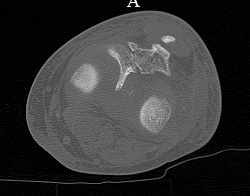

скан, который, на мой взгляд наиболее интересен

Серия КТ сканов в аппарате

Голень-41-С3.1 - полный внутрисуставной и метафизарный оскольчатый перелом с доминантным повреждением наружного мыщелка, с импрессией центральной части плато. Первичная тактика полный респект по АО и ОТА. на фоне лигаметотаксиса выполнено КТ, которое четко детализирует повреждение и определяет дальнейшую тактику.